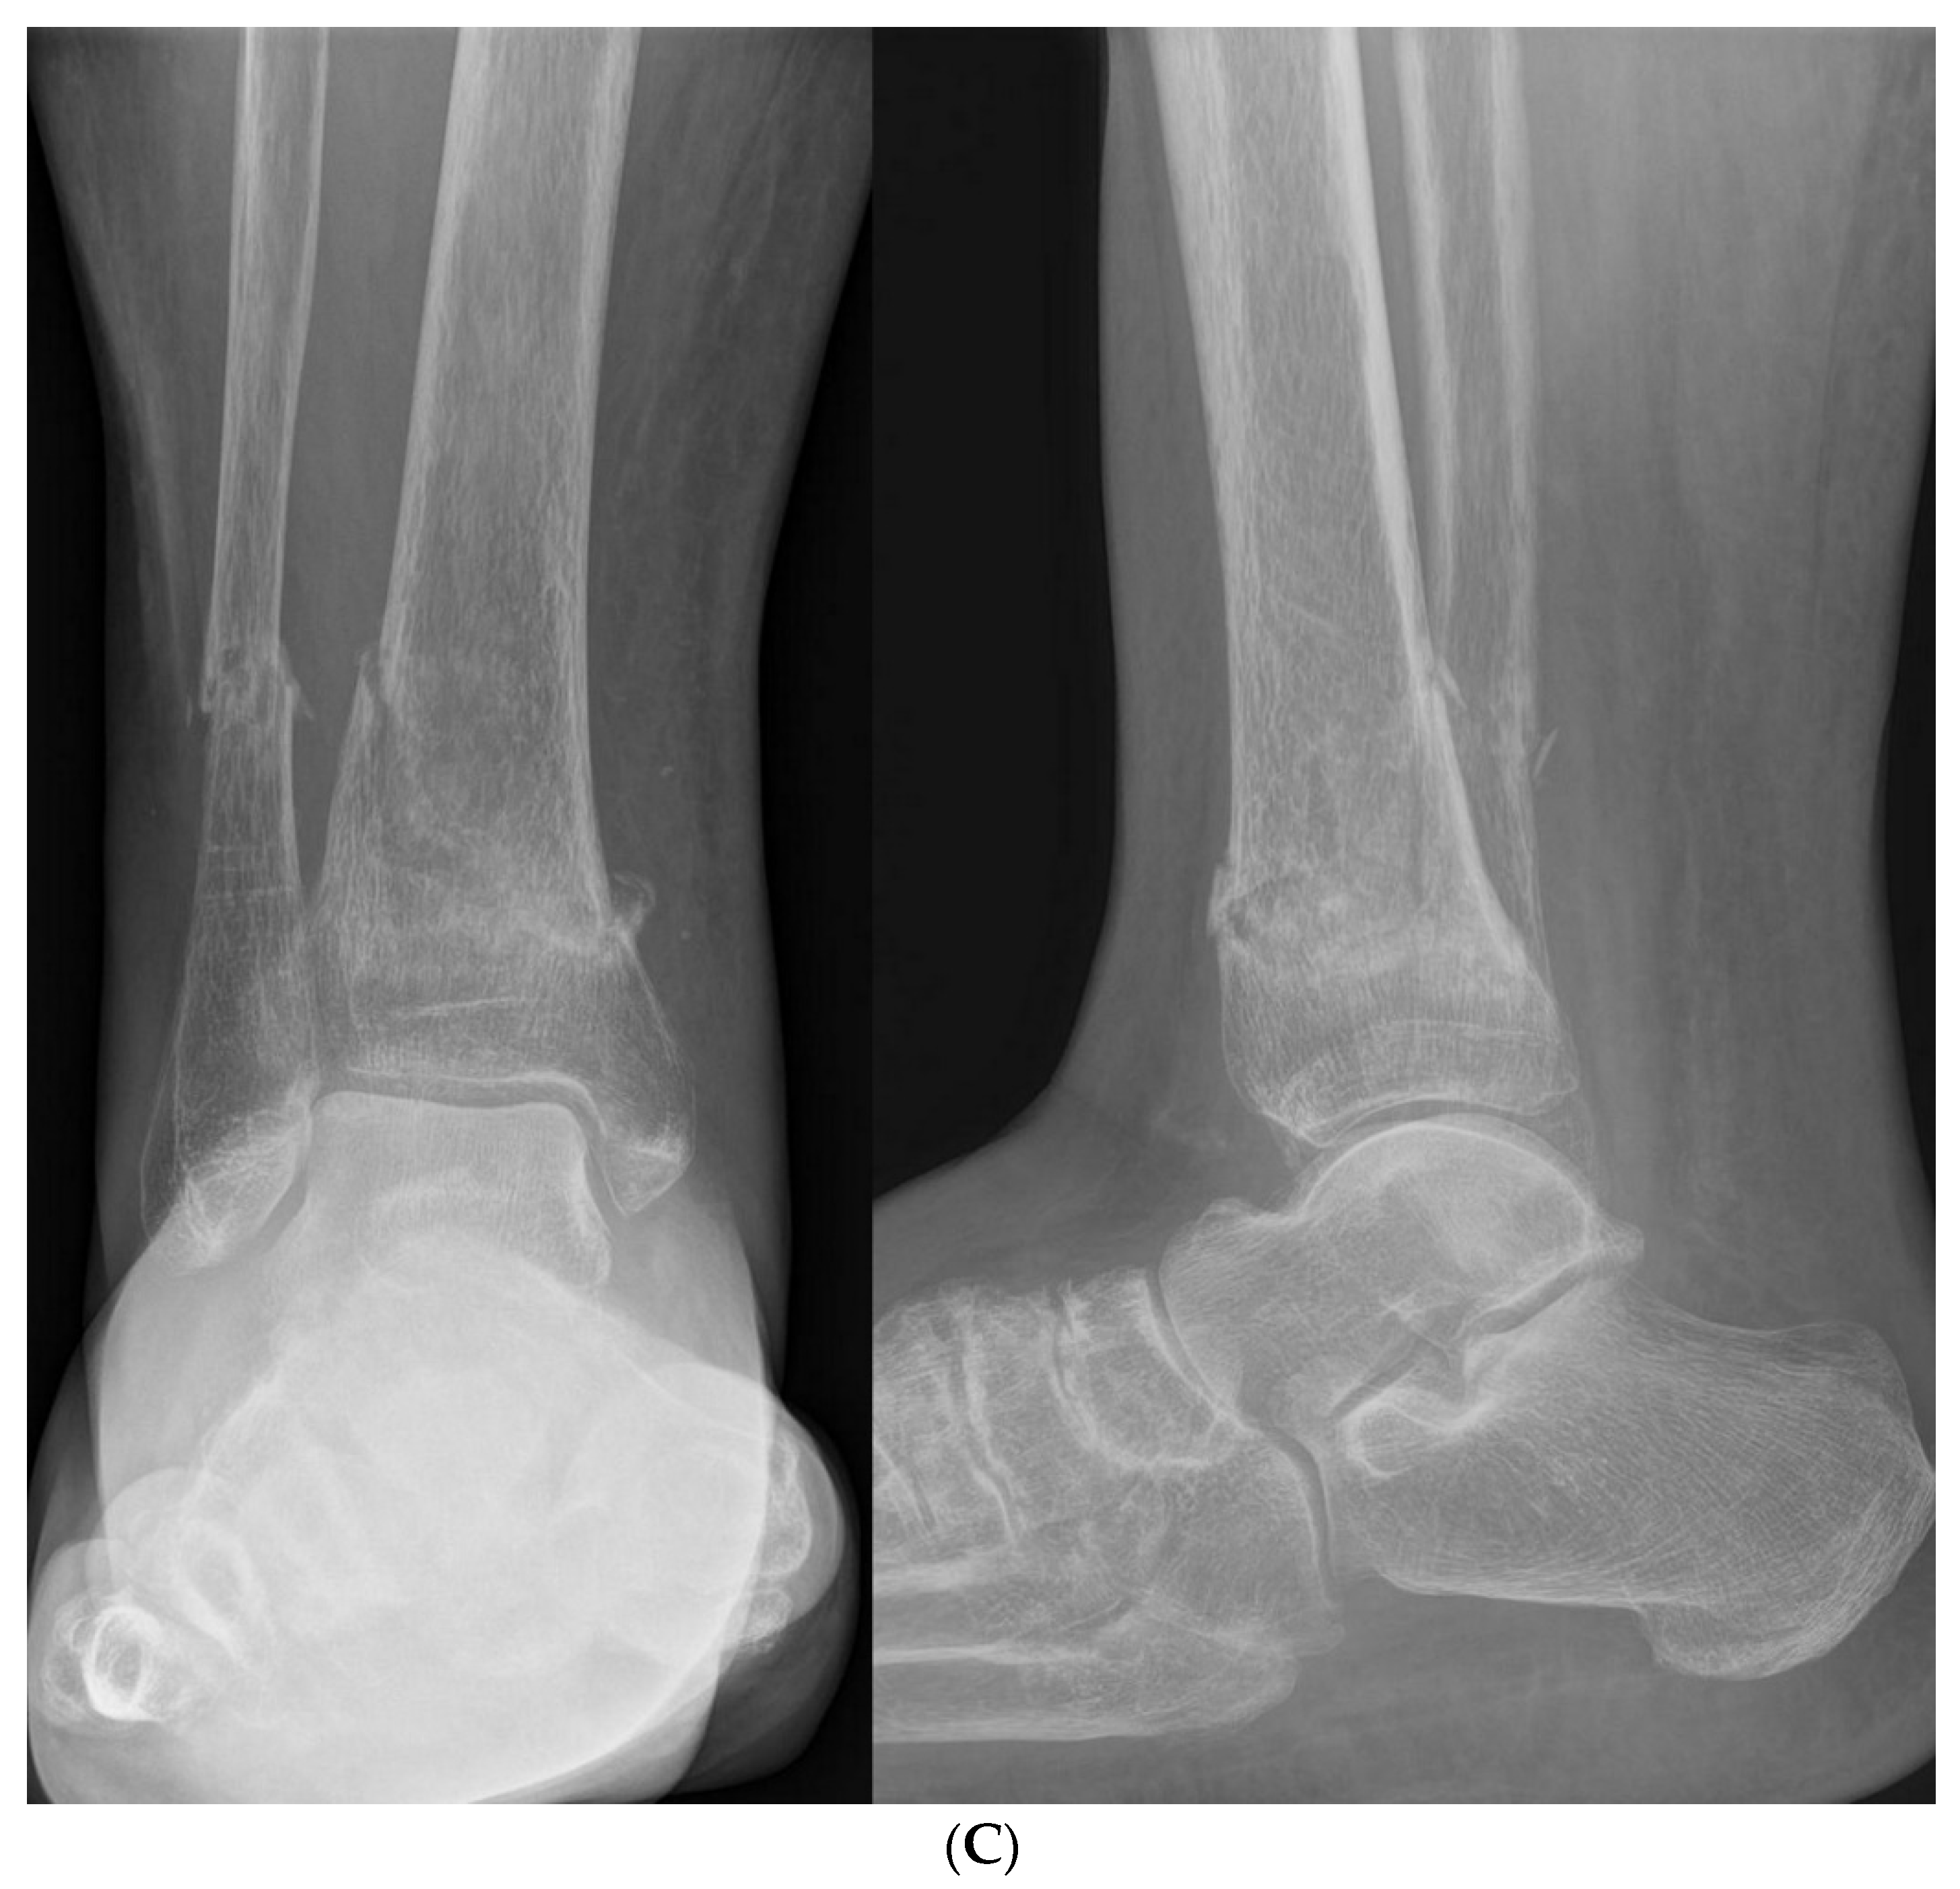

3.2.3. Ligament Injuries

- Gribble, P.A.; Bleakley, C.M.; Caulfield, B.M.; Docherty, C.L.; Fourchet, F.; Fong, D.T.P.; Hertel, J.; Hiller, C.E.; Kaminski, T.W.; McKeon, P.O.; et al. 2016 consensus statement of the International Ankle Consortium: Prevalence, impact and long-term consequences of lateral ankle sprains. Br. J. Sports Med. 2016, 50, 1493–1495. [Google Scholar] [CrossRef] [PubMed]

- Gribble, P.A.; Bleakley, C.M.; Caulfield, B.M.; Docherty, C.L.; Fourchet, F.; Fong, D.T.P.; Hertel, J.; Hiller, C.E.; Kaminski, T.W.; McKeon, P.O.; et al. Evidence review for the 2016 International Ankle Consortium consensus statement on the prevalence, impact and long-term consequences of lateral ankle sprains. Br. J. Sports Med. 2016, 50, 1496–1505. [Google Scholar] [CrossRef]

- Doherty, C.; Delahunt, E.; Caulfield, B.; Hertel, J.; Ryan, J.; Bleakley, C. The incidence and prevalence of ankle sprain injury: A systematic review and meta-analysis of prospective epidemiological studies. Sports Med. 2014, 44, 123–140. [Google Scholar] [CrossRef]

- Szczepaniak, J.; Ciszkowska-Łysoń, B.; Śmigielski, R.; Zdanowicz, U. Value of ultrasonography in assessment of recent injury of anterior talofibular ligament in children. J. Ultrason. 2015, 15, 259–266. [Google Scholar] [CrossRef]